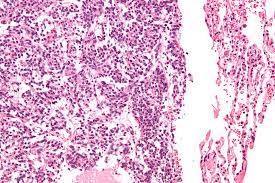

They are most commonly located in the gastrointestinal tract and can synthesize a variety of hormones (especially. Carcinoid tumors usually do not cause symptoms in the early stages. Atlas of tumor pathology (3rd series). Guidelines for the diagnosis and management of carcinoid tumors. Carcinoid tumors are noncancerous (benign) or cancerous (malignant) growths. Carcinoid tumors are of neuroendocrine origin and derived from primitive stem cells in the gut wall carcinoid tumors can be nonfunctioning presenting as a tumor mass or functioning i.e. Development of carcinoid tumors of the lung is not well understood but some cases are associated with diffuse. A lung carcinoid tumor is a type of cancerous tumor made up of neuroendocrine cells. Signs and symptoms of carcinoid syndrome may include facial. In some cases, metastasis may occur. Carcinoid tumors in the lungs or gut often have no symptoms, however, they may cause carcinoid syndrome. Carcinoid tumor is a rare type of tumor that usually grows slowly. Carcinoid and other neuroendocrine tumors.

Carcinoid and other neuroendocrine tumors. In tumors of the lower respiratory tract. Carcinoid tumors often don't cause signs and symptoms until late in the disease. Two thirds of carcinoid tumours occur somewhere in the gastrointestinal tract. Carcinoid tumors arise from endocrine amine precursor uptake and.